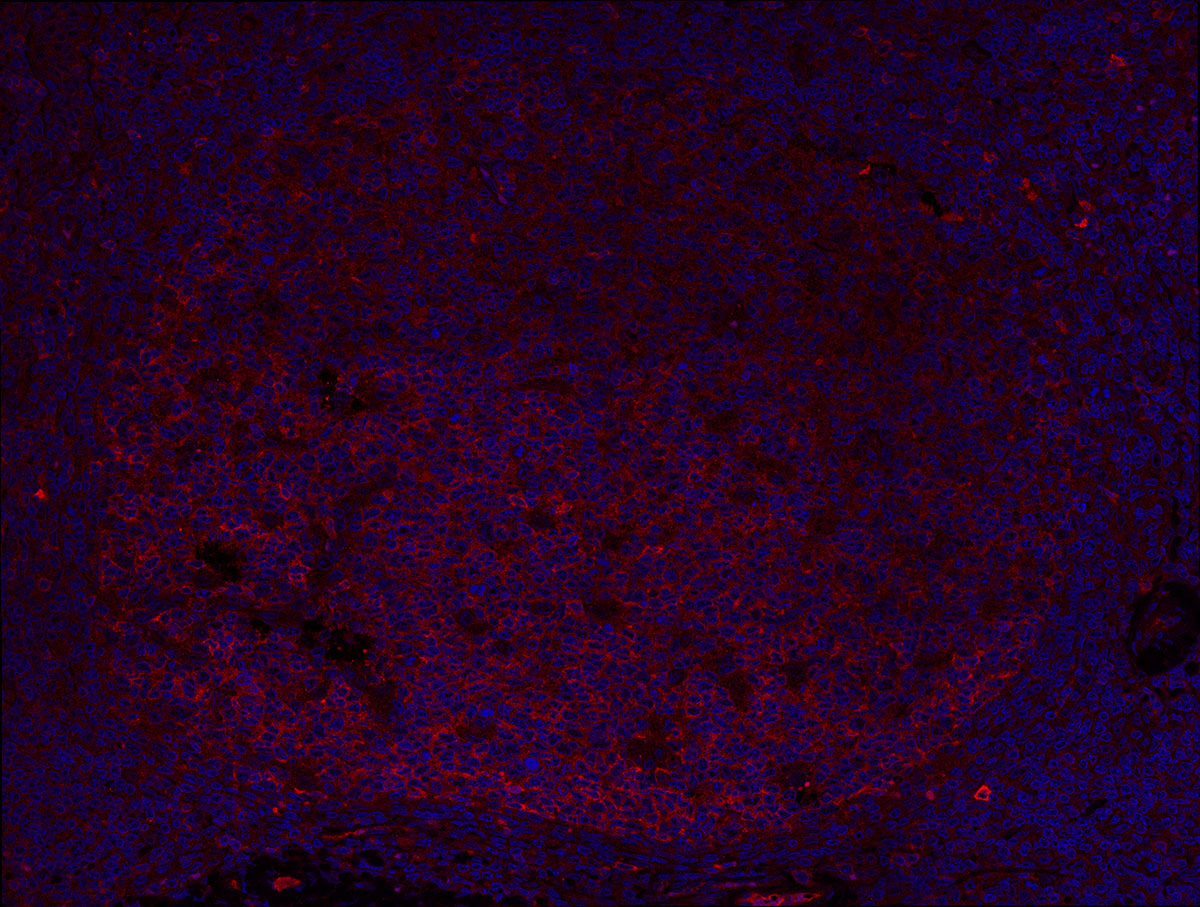

AICDA (AID) antibody IF Characterisation: Endogenous expression

Single immunofluorescence staining of clone JUA51E (red) in human paraffin embedded tonsil showing AID expression in germinal centres.